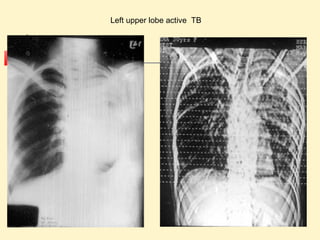

Left upper lobe active TB

Left upper lobeactive TB